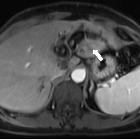

intrahepatische Cholelithiasis

Cholezystolithiasis Radiopaedia • CC-by-nc-sa 3.0 • de

MRI

- T1-weighted 3D fast spoiled gradient echo (3D FSPGR):

- pigmented stones (hyperintense)

- cholesterol stones (hypointense)

- T2: signal void or low signal outlined by markedly hyperintense bile within the gallbladder

- MRCP: focus of signal void inside the gallbladder